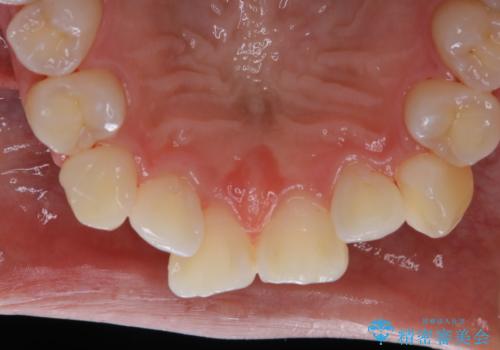

矯正治療開始前のPMTC

- 矯正カウンセリング、矯正検査後にクリーニング希望で来院されました。しばらく歯科医院にて、クリーニングを行ってなく、歯石やステインが気になるとのことでした。PMTC(自費クリーニング)30分コースを行いました。

矯正治療は、歯を動かすため歯ぐきにもかなりの負担がかかります。そのため歯列矯正の前にはしっかりとしたクリーニングを行い、歯ぐきのコンディションも整えることが大切です。また、歯石やステイン(着色)が歯についたままだと、矯正の装置が、適切に設置できなかったり、装置が外れやすくなってしまったりとトラブルの原因になることがあります。矯正治療中に歯周病や虫歯にならないためにも、専門的なクリーニングを行うことが大切です。